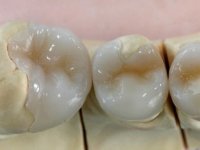

After it, the dental technician constructed the ceramic overlays to rehabilitate 47-44, that were bonded while testing the CAD-CAM zirconia frameworks in the maxilla. In this session, the provisional FPDs in the 1st and 2nd quadrant were removed separately to allow a bite-registration with the inter-maxillary relations that the patient supported with the provisional restorations, and colour was evaluated and registered.

In the bisque-bake try-in session, the dental technician was present in the dental office to observe and register in the bisque-bake try-in itself the modifications that had to be done, mainly concerning anatomical design.